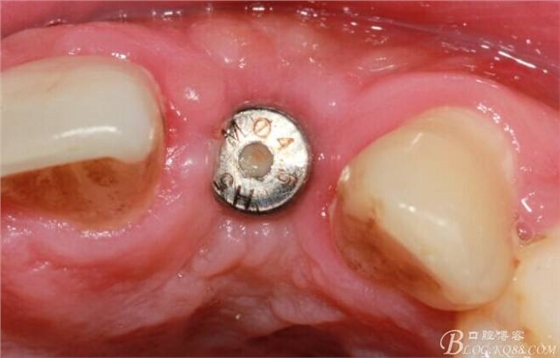

翻開(kāi)后驚喜的發(fā)現(xiàn),術(shù)區(qū)成骨非常好,去除部分骨才暴露那顆長(zhǎng)鈦釘。

取出影響種植入路的長(zhǎng)鈦釘。

擴(kuò)孔。

骨擠壓。

植入植體。